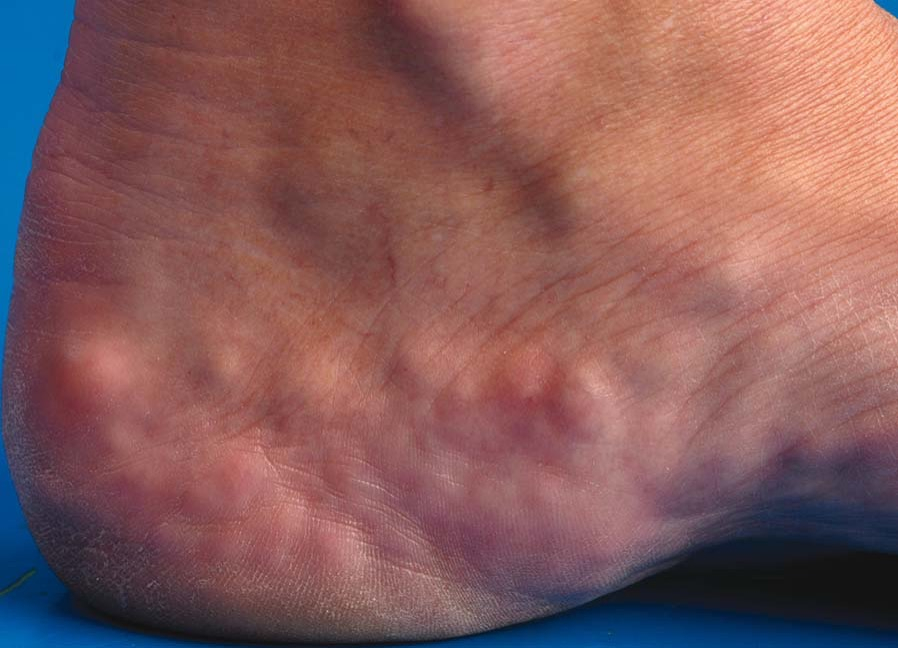

Wanneer vetweefsel uit de stijvere ondersteunende weefsels breekt en voor het oog duidelijk wordt, wordt de term voor deze aandoening piëzogene papuli genoemd. De term piezo komt van het Latijnse woord piezein, wat betekent comprimeren. Aan de onderkant van de voet fungeert vetweefsel als schokdemping voor de botten en gewrichten. Bij gaan en staan wordt er neerwaartse druk op het vetweefsel van de voetbodem uitgeoefend. Het vetweefsel wordt tegen de huid gedrukt en zo vormt het piëzogene papuli.

Mensen met het Ehlers-Danlos-syndroom (een bindweefselaandoening), zijn vatbaarder voor deze papuli, net als degenen die voor lange tijd staan. Atleten, vooral lange afstandslopers, ontwikkelen vaak piëzogene papulie. Ze zijn niet leeftijdsgebonden en hebben geen invloed op een specifieke etnische groep. Soms kan obesitas een oorzakelijke factor zijn.

In de meeste gevallen zijn deze piëzogene papuli pijnvrij en onschuldig. Soms is er pijn aanwezig als de zenuwen samen met het vetweefsel door het fascia heen komen. Deze pijnlijke papels zijn meestal iets groter dan 2 cm en komen minder vaak voor. Als er pijn aanwezig is, wordt dit gewoonlijk geassocieerd met een voorgeschiedenis van langdurig staan. Wanneer behandeling vereist is als gevolg van piëzogene papulie die tegen een schoen wrijft, zal er in eerste instantie gedacht worden aan een compressiekous, sportinlay waarbij de hiel zeer nauw omsloten wordt middels een kuipzool en een goede stevige dagelijkse schoen met stevige hielkap.